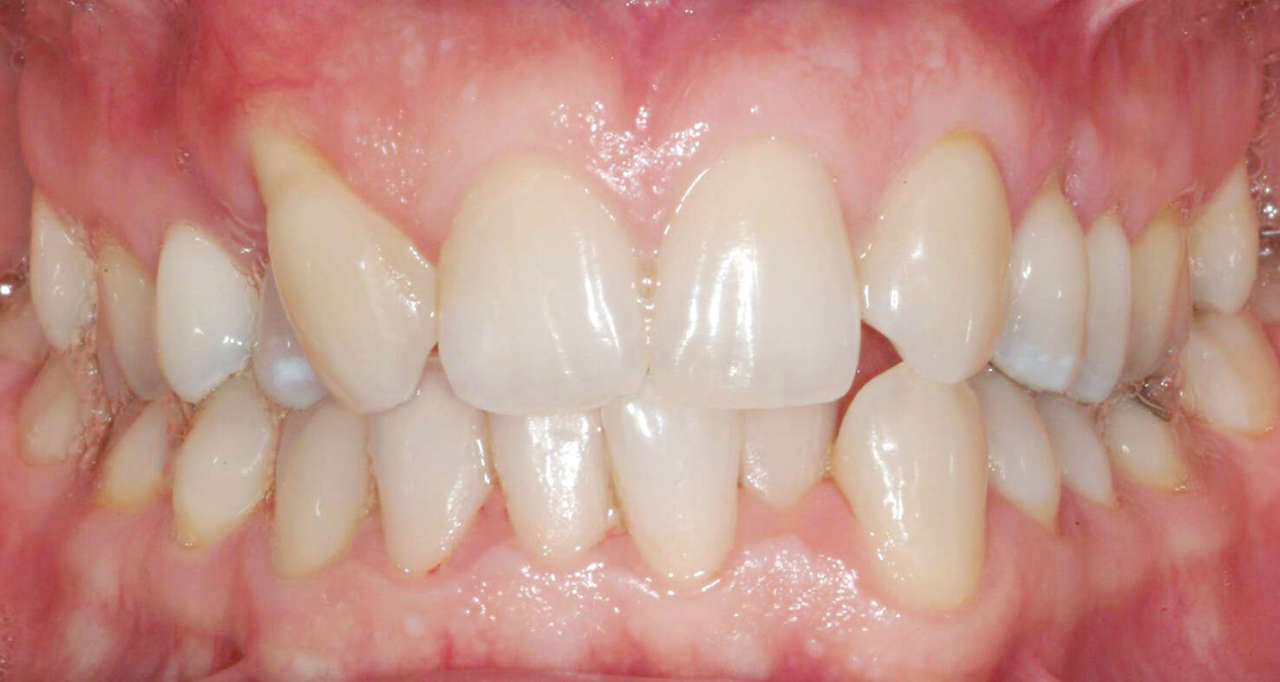

Una paziente di sesso femminile, 38 anni, già trattata ortodonticamente presso altra sede con apparecchiatura fissa a entrambe le arcate in età adolescenziale senza successiva applicazione di alcuna contenzione, si presenta alla nostra attenzione perché insoddisfatta dell’estetica del sorriso; richiede una valutazione per un trattamento ortodontico con apparecchiatura fissa linguale per la presenza di affollamento dentale a entrambe le arcate e difficoltà a mantenere una adeguata igiene orale; si riscontrano agenesia di entrambi gli incisivi laterali superiori (1.2 e 2.2) e del secondo premolare inferiore destro (4.5). Presentiamo la risoluzione del caso mediante trattamento ortodontico estrattivo a entrambe le arcate, eseguito con apparecchiatura linguale invisibile 2D e meccanica asimmetrica e seguito a medio termine da riabilitazione implanto-protesica e contenzione fissa.

Per formulare corretta diagnosi e piano di cura, lo studio del caso ha previsto la raccolta di documentazione completa standard, ovvero fotografie del viso e intraorali (Figure 1a-e), radiografia panoramica e teleradiografia del cranio in proiezione laterale (Figure 2a-b) per la relativa analisi cefalometrica e modelli di studio.

La valutazione clinica e gli esami effettuati confermano la presenza di agenesia degli incisivi laterali superiori (1.2 e 2.2) e del secondo premolare inferiore destro (4.5).